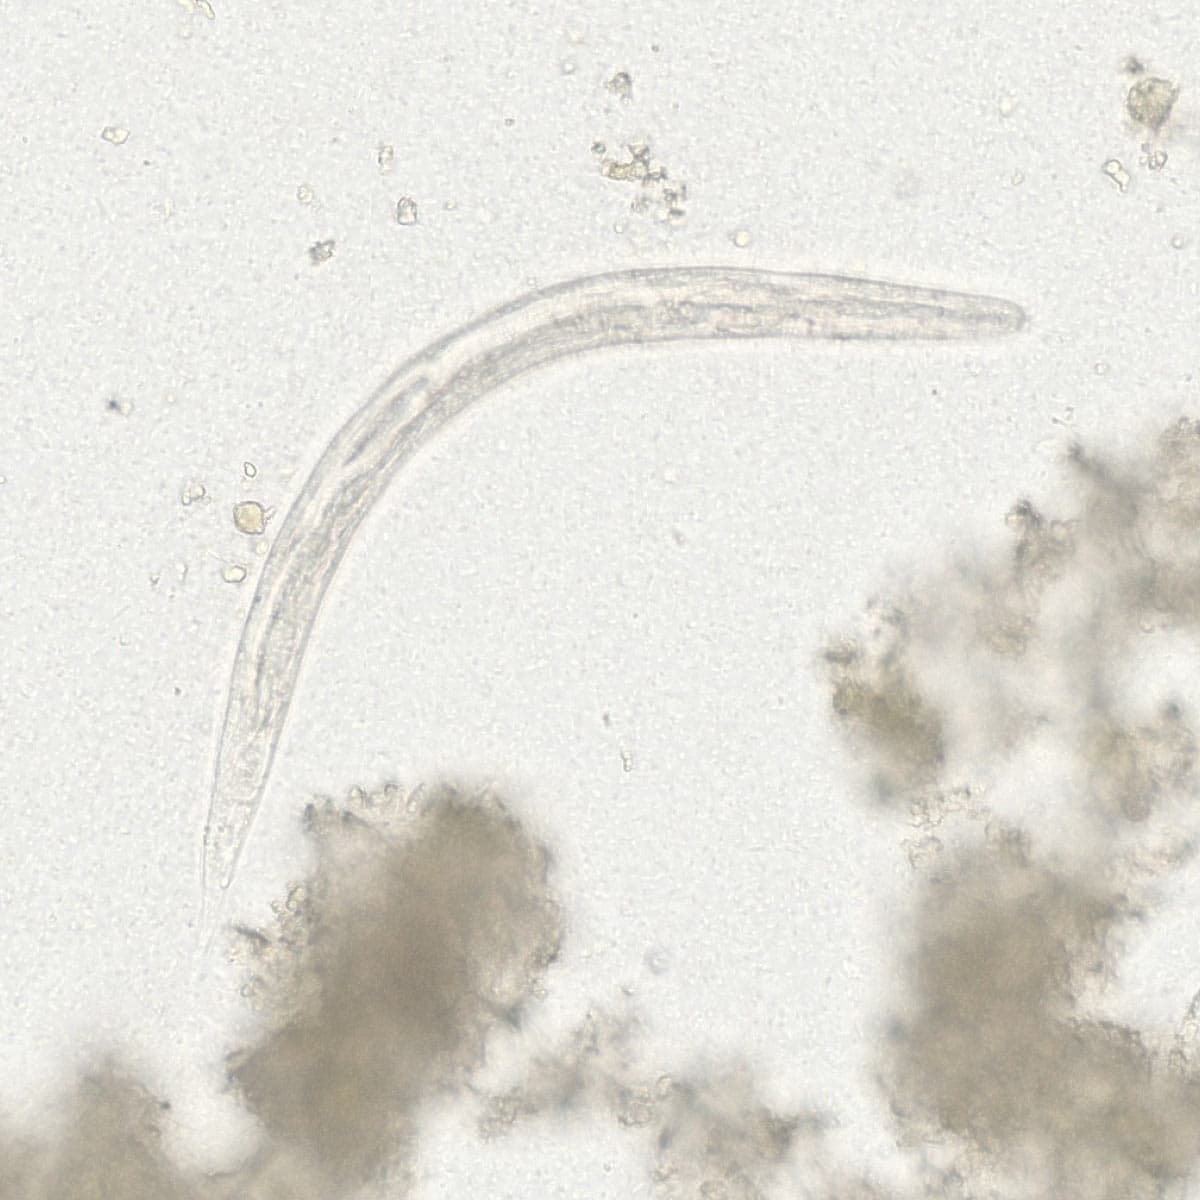

Automatic detection over 30 species

Built on worldwide parasite-positive specimens, ParaScout AI identifies a vast number of parasite species, including those that are clinically rare or challenging to find.

Evidence of results detection

Visual evidence is provided for every diagnosis.